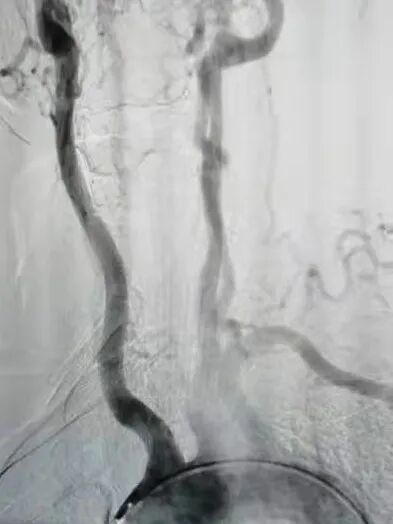

在征得王先生及家人同意后,魏主任组织介入团队进行术前讨论,依据患者病情拟定了详细的手术方案,手术由魏主任亲自操作,在手术中意想不到的遇到了重重困难:一是斑块硬开通困难,二是斑块脱落形成栓塞,三是病灶在夹层,四是支架不能堵塞椎动脉等,给手术带来很大风险,凭借多年的临床实践,终于把血管开通、支架植入。后经造影显示:右锁骨下动脉支架置入后恢复前向血流,不再盗血,手术历时4个小时,整个过程可谓“惊心动魄”。